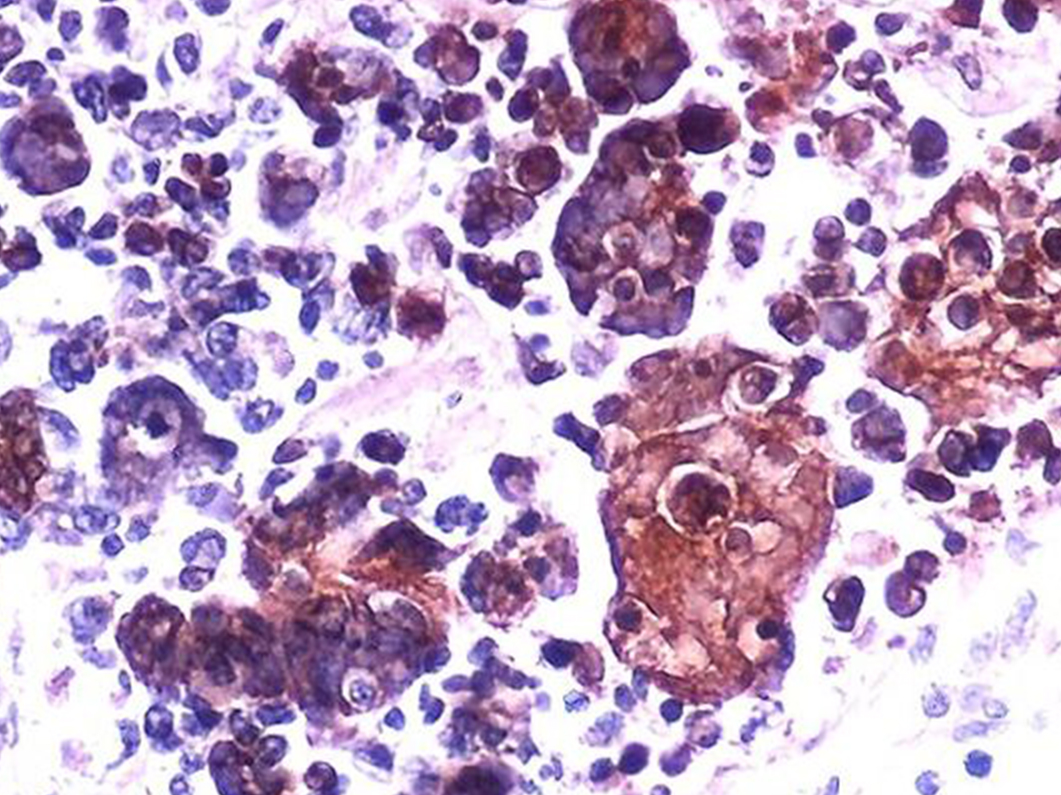

Genital Warts

Genital warts are virus-induced warts that appear around the genitals or anus, often spreading in a cauliflower-like shape. Among viral sexually transmitted diseases, genital warts are one of the most treatable STDs. If genital warts occur, the partner’s genitals should also be examined, and sexual contact should be avoided until both parties have completed treatment.